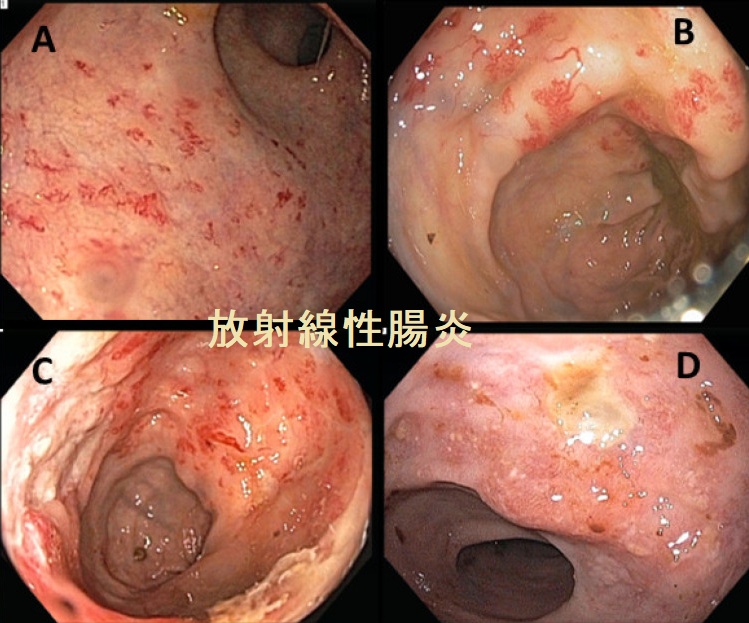

放射線性腸炎(放射線治療誘発性腸炎)とは、骨盤内の癌(子宮頸癌、前立腺癌など)の放射線治療後に起こる腸炎です。主に、直腸やS状結腸の腸粘膜障害。

放射線性腸炎は、

- 早期障害(治療中に起こる):腹痛、吐き気、下痢、肛門痛など。腸管の炎症や浮腫が原因で、放射線治療終了後に改善することが多い。治療は対症療法、ステロイド薬投与

- 晩期障害(治療後数か月~数年後に起こる):血便、下痢、肛門痛、便秘・排便困難・腸閉塞など。血管損傷や線維化が原因で、症状は持続・悪化。治療は内視鏡治療(レーザー治療、止血など)や、薬物療法(サラゾスルファピリジンなど)、外科手術

放射線性腸炎の大腸内視鏡像は、直腸・S状結腸粘膜の浮腫・発赤・びらん・潰瘍・点状出血斑・血管透見性消失・毛細血管の拡張